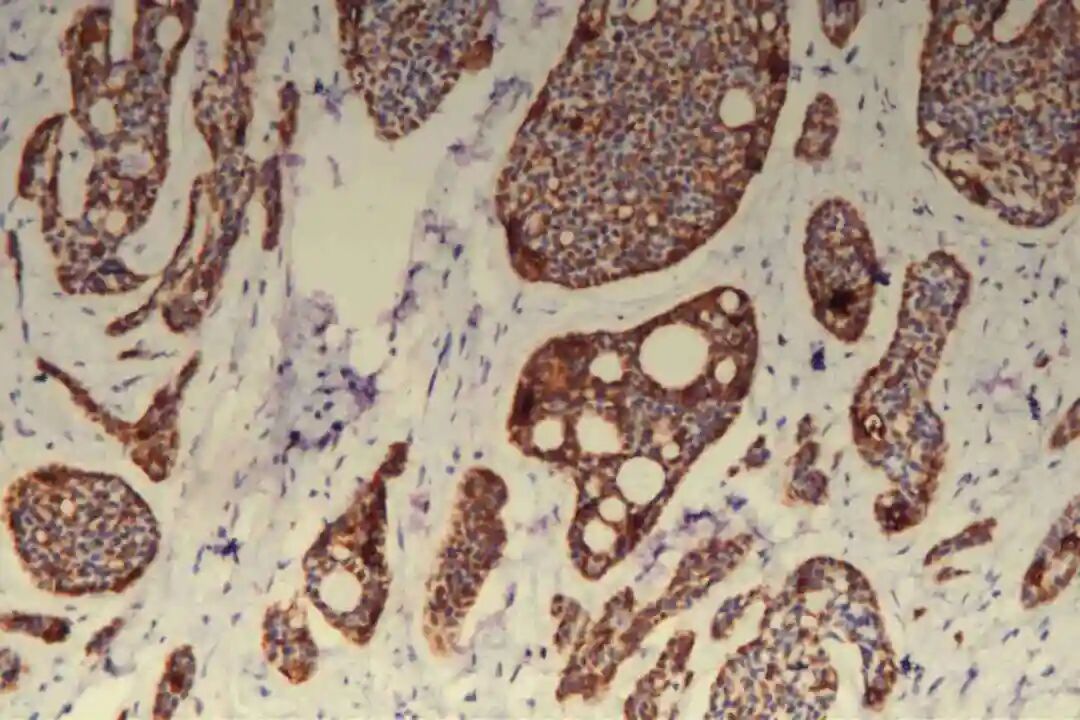

免疫组化:09号片:ER(-),PR(-),Her-2(2+),CK7(腺上皮+),CD117(+),CK5/6(肌上皮+),P63(肌上皮+),GCDFP-15(-),GATA3(-),S-100(+,显示神经侵犯),P120(膜+),E-Cadherin(膜+),P53(野生表型),Ki67(+)10%。

腺上皮细胞主要表达细胞角蛋白(CK)家族相关标志物,其中CK7、CK8/18呈弥漫阳性表达,CK19呈局灶性阳性表达,这是确认腺上皮细胞来源的核心依据;部分病例中,腺上皮细胞可表达CD117(c-Kit),呈弥漫或局灶阳性,CD117在实体型区域的阳性表达率高于经典型区域,可作为实体型PACC的辅助鉴别指标。此外,腺上皮细胞不表达雌激素受体(ER)、孕激素受体(PR)及人表皮生长因子受体2(Her-2),即“三阴性”表型,这是PACC与激素受体阳性乳腺癌、Her-2阳性乳腺癌的重要区别,也是临床治疗方案选择的重要依据之一。

肌上皮细胞是PACC的重要组成部分,其标志物表达是诊断PACC的关键,主要表达p63、P40、平滑肌肌动蛋白(SMA)、肌动蛋白(Actin)及S-100蛋白,其中p63、P40呈弥漫阳性表达,SMA、S-100蛋白呈局灶或弥漫阳性表达。